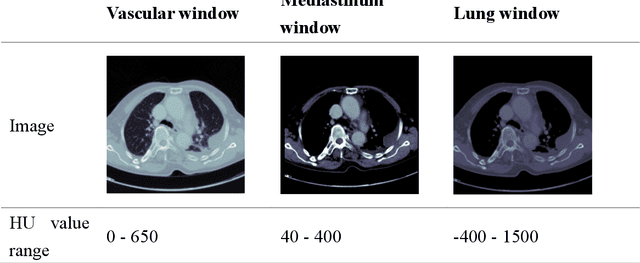

Abstract:The purpose of this research is to develop a system that generates simulated computed tomography pulmonary angiography (CTPA) images clinically for pulmonary embolism diagnoses. Nowadays, CTPA images are the gold standard computerized detection method to determine and identify the symptoms of pulmonary embolism (PE), although performing CTPA is harmful for patients and also expensive. Therefore, we aim to detect possible PE patients through CT images. The system will simulate CTPA images with deep learning models for the identification of PE patients' symptoms, providing physicians with another reference for determining PE patients. In this study, the simulated CTPA image generation system uses a generative antagonistic network to enhance the features of pulmonary vessels in the CT images to strengthen the reference value of the images and provide a basis for hospitals to judge PE patients. We used the CT images of 22 patients from National Cheng Kung University Hospital and the corresponding CTPA images as the training data for the task of simulating CTPA images and generated them using two sets of generative countermeasure networks. This study is expected to propose a new approach to the clinical diagnosis of pulmonary embolism, in which a deep learning network is used to assist in the complex screening process and to review the generated simulated CTPA images, allowing physicians to assess whether a patient needs to undergo detailed testing for CTPA, improving the speed of detection of pulmonary embolism and significantly reducing the number of undetected patients.

Abstract:This study established a feature-enhanced adversarial semi-supervised semantic segmentation model to automatically annotate pulmonary embolism lesion areas in computed tomography pulmonary angiogram (CTPA) images. In current studies, all of the PE CTPA image segmentation methods are trained by supervised learning. However, the supervised learning models need to be retrained and the images need to be relabeled when the CTPA images come from different hospitals. This study proposed a semi-supervised learning method to make the model applicable to different datasets by adding a small amount of unlabeled images. By training the model with both labeled and unlabeled images, the accuracy of unlabeled images can be improved and the labeling cost can be reduced. Our semi-supervised segmentation model includes a segmentation network and a discriminator network. We added feature information generated from the encoder of segmentation network to the discriminator so that it can learn the similarity between predicted mask and ground truth mask. This HRNet-based architecture can maintain a higher resolution for convolutional operations so the prediction of small PE lesion areas can be improved. We used the labeled open-source dataset and the unlabeled National Cheng Kung University Hospital (NCKUH) (IRB number: B-ER-108-380) dataset to train the semi-supervised learning model, and the resulting mean intersection over union (mIOU), dice score, and sensitivity achieved 0.3510, 0.4854, and 0.4253, respectively on the NCKUH dataset. Then, we fine-tuned and tested the model with a small amount of unlabeled PE CTPA images from China Medical University Hospital (CMUH) (IRB number: CMUH110-REC3-173) dataset. Comparing the results of our semi-supervised model with the supervised model, the mIOU, dice score, and sensitivity improved from 0.2344, 0.3325, and 0.3151 to 0.3721, 0.5113, and 0.4967, respectively.

Abstract:This study was conducted to develop a computer-aided detection (CAD) system for triaging patients with pulmonary embolism (PE). The purpose of the system was to reduce the death rate during the waiting period. Computed tomography pulmonary angiography (CTPA) is used for PE diagnosis. Because CTPA reports require a radiologist to review the case and suggest further management, this creates a waiting period during which patients may die. Our proposed CAD method was thus designed to triage patients with PE from those without PE. In contrast to related studies involving CAD systems that identify key PE lesion images to expedite PE diagnosis, our system comprises a novel classification-model ensemble for PE detection and a segmentation model for PE lesion labeling. The models were trained using data from National Cheng Kung University Hospital and open resources. The classification model yielded 0.73 for receiver operating characteristic curve (accuracy = 0.85), while the mean intersection over union was 0.689 for the segmentation model. The proposed CAD system can distinguish between patients with and without PE and automatically label PE lesions to expedite PE diagnosis